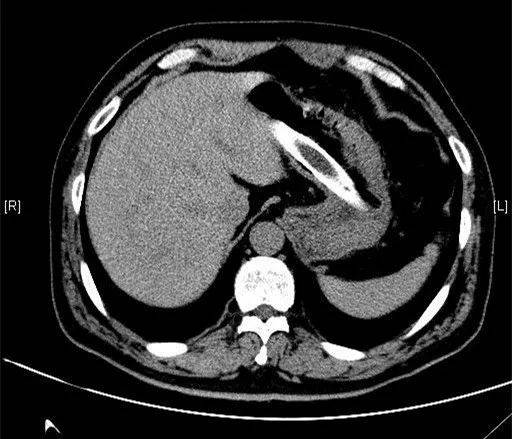

该患者今年58岁 , 3个月前 , 他将塑料衣架折断后吞进肚子里 , 同时塞进去的还有一节塑料管 。 近日该患者感觉肚子隐痛才来医院就诊 。 经CT扫描和病人自述 , 大家都惊呆了 。

如误吞异物 , 请及时就医 。 采用大口吞食馒头或米饭、喝醋等方法都是错误的 , 会加重消化道黏膜的损伤 。 如果发生出血、穿孔等情况 , 还会危及生命 。